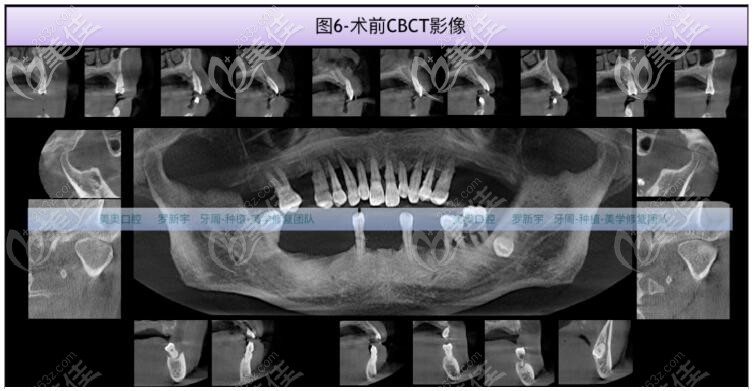

在罗医生的面诊,结合CT拍片检查,大爷的缺牙区骨质II-III类,骨量充足,但15、14、13、12、11、21、22、23、24、25、37、36、48中到重度骨吸收。17、33、43轻中度骨吸收。

术前1周检查血常规、凝血功能及传染5项,全口牙周基础治疗后,大爷在美奥口腔做了NOBEL诺贝尔全口即刻种植牙。